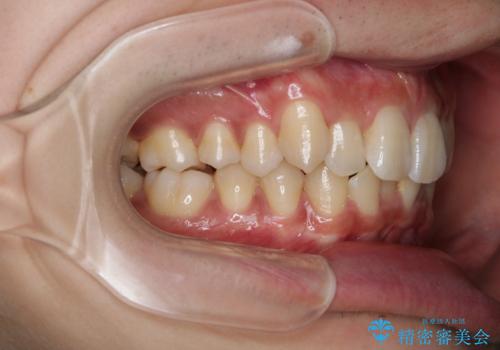

インビザライン:前歯のがたつきと噛み合わせの治療

- 前歯のがたつきが気になるとご相談にいらした方です。左の奥歯の噛み合わせのズレも認められたため、インビザライン治療にて改善しました。

主訴である前歯のガタつきだけでなく、奥歯の噛み合わせからしっかり治療したため、治療期間が長めとなりました。患者様ご本人としては治療の途中で一時的にモチベーションが下がったこともあったようですが、最後まで頑張って続けて頂けたことで噛み合わせ及び見た目の改善を行うことが出来ました。